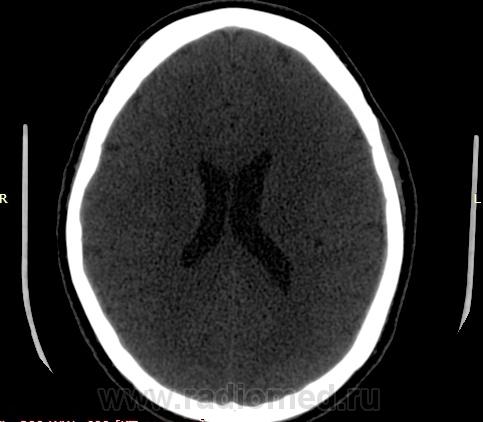

Прошу разрешить спор. По КТ - норма. Женщина, 1967г.р., жалобы на головную боль, больше в затылочной области. По-моему, не КТ-шное это дело но всеж...

Открыл. В мозгу ничего осбенного не увидел. По поводу Киари ничего не скажу, на аксиалах не вижу, а реконструкции эти срезы не строят Да и отношусь я к этой патологиии как к норме.

Но мне показалось, что всеж, для 1967г.р., не очень норма, придираюсь уже, пора на покой .

Аномалию Арнольда-Киари 1типа.

На МРТ выставили  аномалию Арнольда-Киари 1, нам сказали фу... На что я ответил, что по " ловцу и рыба". Во - первых, линию на КТ провести сложно ( в данном иссл.), во-вторых - естественные артефакты костей основания. И вообще пошли на...МРТ! Но осадок остался.